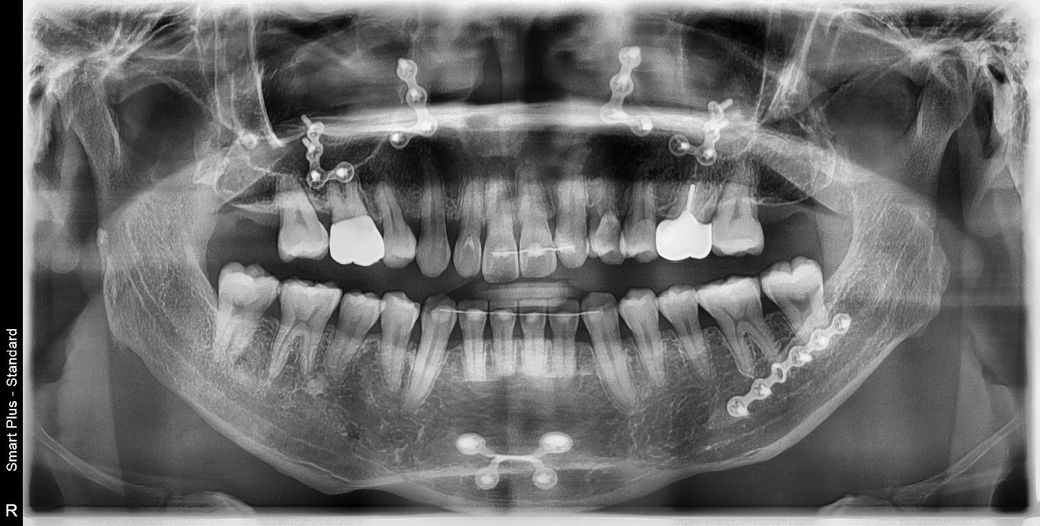

치아사진 분석좀 해주세요(사진첨부)

상악 우측송곳니(사진은좌측)

철사가있을때와 반제거했을때 비교

철사가있을때 이미 벌어져있던건지 아니면 제거후 벌어진건지 진문가소견좀 주세요

사진확대하면 잘보입니다

• 1번 째 사진

철사가있을때 이미 벌어져있던 부분이 보입니다. 위 사진만으로 명확한 판단은 힘듭니다.

상악우측 송곳니 살짝 이동은 있어보입니다 다만 정확히 비교하려면 다른 기록(캐스트, 치근단 엑스레이사진) 필요합니다